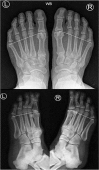

The terminology 'Morton's neuroma' may represent a simplification of the clinical condition as the problem may not be a benign tumour of the nerve, but neuropathic foot pain associated with the interdigital nerve.Foot and ankle pathomechanics leading to metatarsalgia, clinical examination and differential diagnosis of the condition and imaging of the condition, for differential diagnosis, are discussed.Nonoperative management is recommended initially. Physiotherapy, injections (local anaesthetic, steroid, alcohol), cryotherapy, radiofrequency ablation and shockwave therapy are discussed.Operative treatment is indicated after nonoperative management has failed. Neuroma excision has been reported to have good to excellent results in 80% of patients, but gastrocnemius release and osteotomies should be considered so as to address concomitant problems.Key factors in the success of surgery are correct diagnosis with recognition of all elements of the problem and optimal surgical technique. Cite this article: EFORT Open Rev 2019;4:14-24. DOI: 10.1302/2058-5241.4.180025.